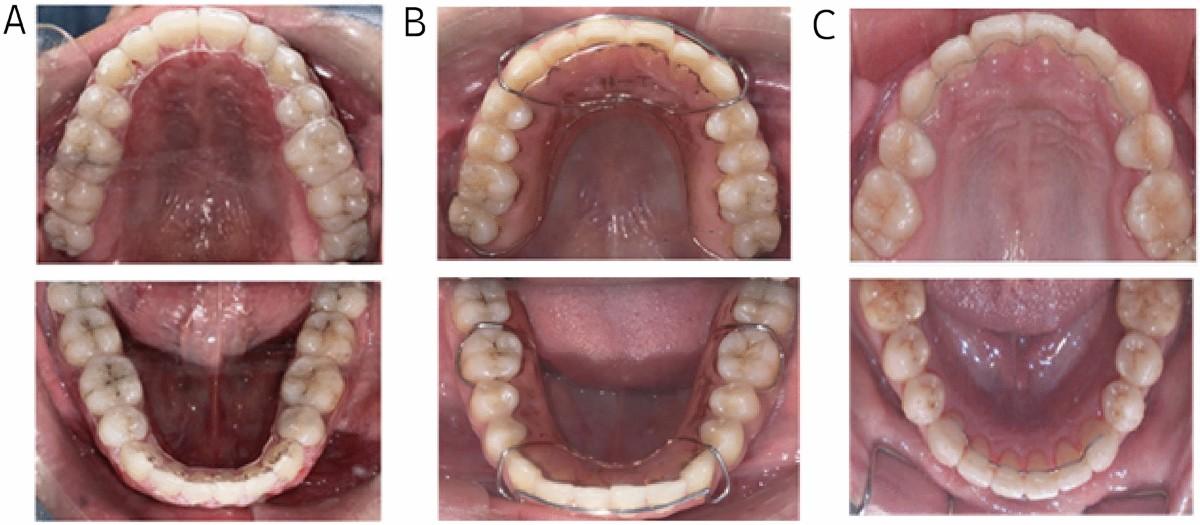

Tái phát sau niềng răng thường được giải thích đơn giản là do cơ địa hoặc do không đeo hàm duy trì đầy đủ, nhưng trên thực tế, yếu tố quyết định lại nằm ở vị trí răng sau điều trị có nằm trong vùng cân bằng lực sinh lý hay không. Răng luôn chịu tác động đồng thời của lực môi, lực má và lực lưỡi, và chỉ khi vị trí của răng cân bằng với các lực này thì nó mới có thể duy trì ổn định lâu dài.

Nếu răng được đặt ở vị trí vượt ra ngoài vùng cân bằng, hệ thống sẽ có xu hướng tự điều chỉnh trở lại trạng thái cũ, bất kể có sử dụng hàm duy trì hay không. Trong X-Matrix, yếu tố ổn định được kiểm soát bằng cách thiết kế vị trí răng dựa trên cung xương thật, kiểm soát trục răng và hạn chế các dịch chuyển vượt quá khả năng thích nghi của mô, từ đó đảm bảo rằng kết quả đạt được không chỉ tồn tại tại thời điểm tháo niềng mà còn duy trì được theo thời gian.

Tiêu chuẩn ổn định được đánh giá dựa trên vị trí răng trong vùng cân bằng lực sinh lý. Răng sau điều trị không chỉ giữ được nhờ khí cụ duy trì mà phải có khả năng tự ổn định trong môi trường lực của môi, má và lưỡi, hạn chế tối đa nguy cơ tái phát.